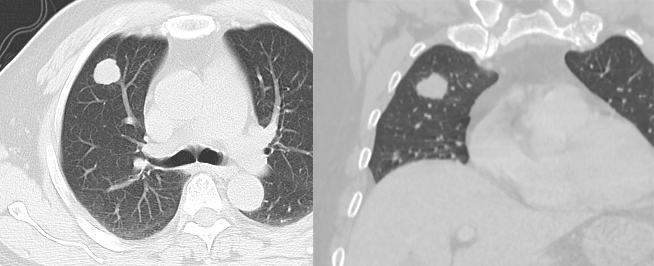

10 種肺轉(zhuǎn)移瘤的 CT 表現(xiàn)

10種肺轉(zhuǎn)移瘤的CT表現(xiàn)肺是腫瘤細(xì)胞的濾過器官,肺轉(zhuǎn)移極為常見,是發(fā)生轉(zhuǎn)移性腫瘤最多的部位。肺轉(zhuǎn)移瘤典型表現(xiàn)為隨機(jī)分布的多發(fā)邊緣光滑、大小不等的球形結(jié)節(jié)(血行轉(zhuǎn)移)和小葉間隔串珠狀增厚(淋巴道轉(zhuǎn)移)。符合上述表現(xiàn)的轉(zhuǎn)移瘤一般認(rèn)為比較典型,多能明確診斷,但臨床常常遇到不典型肺轉(zhuǎn)移瘤,需與其他病變鑒別。常見的不典型表現(xiàn)有單發(fā)肺轉(zhuǎn)移、空洞性肺轉(zhuǎn)移瘤、肺轉(zhuǎn)移瘤并鈣化或骨化、轉(zhuǎn)移瘤內(nèi)含氣支氣管征、栗粒型轉(zhuǎn)移、肺炎型肺轉(zhuǎn)移、轉(zhuǎn)移結(jié)節(jié)周圍模糊影、轉(zhuǎn)移瘤并發(fā)氣胸、腫瘤性動脈栓塞、支氣管內(nèi)膜轉(zhuǎn)移等。1單發(fā)肺轉(zhuǎn)移無惡性腫瘤病史的患者單發(fā)肺轉(zhuǎn)移的發(fā)生率很低(0.4~9.0%),有惡性腫瘤史的患者發(fā)生單發(fā)肺結(jié)節(jié)時(shí)25~46%為轉(zhuǎn)移,且原發(fā)腫瘤多為腺癌或軟組織肉瘤等。Cahan總結(jié)800例肺孤立性腫物提出以下原則:原發(fā)腫瘤為鱗癌時(shí)肺內(nèi)腫物多為原發(fā),為腺癌時(shí)肺內(nèi)原發(fā)和轉(zhuǎn)移的概率各半,原發(fā)為軟組織或骨肉瘤、黑色素瘤時(shí)肺內(nèi)多為轉(zhuǎn)移。CT上單發(fā)轉(zhuǎn)移瘤多數(shù)邊緣光整,符合轉(zhuǎn)移瘤特點(diǎn),少數(shù)邊緣可出現(xiàn)分葉、毛刺等,與原發(fā)腫瘤難以鑒別。2空洞性肺轉(zhuǎn)移瘤文獻(xiàn)報(bào)道空洞型肺轉(zhuǎn)移主要來自鱗癌和腺癌,鱗癌占1/2~2/3,主要來自男性頭頸部與女性生殖器腫瘤,其余為腺癌,主要來自結(jié)腸與乳腺癌。單亦有研究認(rèn)為空洞性轉(zhuǎn)移主要來自腺癌。其產(chǎn)生機(jī)制可能與鱗癌中心角化物排空、腺癌黏液樣退變后黏液排空、腫瘤血供不足引起壞死、腫瘤繼發(fā)膿腫、化療、阻塞性肺氣腫等有關(guān)。空洞性肺轉(zhuǎn)移瘤變化快,短期內(nèi)可見腫瘤增大、增多。CT上空洞型轉(zhuǎn)移結(jié)節(jié)外形上多保持了轉(zhuǎn)移瘤的基本特點(diǎn),即多發(fā)、圓形、邊緣光整。洞壁多薄而均勻,內(nèi)外壁光整,直徑多<1.0cm,部分洞壁厚薄不均,厚壁空洞病變可隨著病灶增大而出現(xiàn)分葉、毛刺及壁結(jié)節(jié)等惡性空洞特點(diǎn),部分空洞型肺轉(zhuǎn)移洞壁可菲薄(稱空泡更合適)。乳腺癌空洞性肺轉(zhuǎn)移。3轉(zhuǎn)移瘤并鈣化或骨化肺結(jié)節(jié)鈣化常常提示良性,常見于肉芽腫性病變。但有些惡性腫瘤肺內(nèi)轉(zhuǎn)移也可發(fā)生鈣化或骨化,轉(zhuǎn)移瘤內(nèi)的鈣化或骨化可見于任何分泌黏液蛋白的腺癌,多見于骨肉瘤、軟骨肉瘤、滑膜肉瘤、結(jié)腸癌、卵巢癌等。鈣化機(jī)制主要包括骨形成不良、營養(yǎng)不良性鈣化和黏液樣鈣化等。CT上鈣化形態(tài)可以為斑片狀、結(jié)節(jié)狀或彌漫分布,難與結(jié)核球、錯(cuò)構(gòu)瘤等鑒別,但鈣化結(jié)節(jié)常多發(fā)且可伴發(fā)典型轉(zhuǎn)移結(jié)節(jié)。骨肉瘤病史。左肺上葉、右肺下葉轉(zhuǎn)移瘤并鈣化/骨化。骨肉瘤并兩肺多發(fā)轉(zhuǎn)移。轉(zhuǎn)移瘤內(nèi)可見斑片、結(jié)節(jié)狀鈣化。4轉(zhuǎn)移瘤內(nèi)含氣支氣管征此類肺轉(zhuǎn)移多見于腺癌,癌細(xì)胞沿完整的肺泡壁及間隔生長,不破壞肺支架結(jié)構(gòu),影像學(xué)表現(xiàn)為含氣支氣管征的結(jié)節(jié)(單發(fā)或多發(fā))、伴含氣支氣管征的實(shí)變、局灶或彌漫的磨玻璃密度等。乳腺癌雙肺多發(fā)轉(zhuǎn)移。左肺上葉一枚轉(zhuǎn)移結(jié)節(jié)內(nèi)可見支氣管走形。5粟粒性轉(zhuǎn)移粟粒狀病灶多見于甲狀腺癌、肝癌、胰腺癌及絨毛膜上皮癌轉(zhuǎn)移。常同時(shí)伴有縱隔淋巴結(jié)腫大及其他臟器轉(zhuǎn)移。左肺上葉肺癌伴雙肺粟粒性轉(zhuǎn)移。6肺炎性肺轉(zhuǎn)移肺炎型的轉(zhuǎn)移病灶邊緣模糊不清,可局限于一肺葉或段并伴「充氣支氣管征」,頗似肺炎樣浸潤陰影,分布在肺周或肺底等。肺炎型轉(zhuǎn)移特征性不大,需與肺炎區(qū)別,明確診斷須靠病理或隨訪??寡字委煙o效,化療后病灶可縮小。部分病灶發(fā)展為較大的腫塊。肺炎型肺轉(zhuǎn)移的產(chǎn)生機(jī)制可能為癌結(jié)節(jié)浸潤生長,結(jié)節(jié)周圍出血或伴癌周阻塞性炎癥所致。胃腺癌根治術(shù)后4年。1年前的胸片顯示右上肺片狀邊緣不清的病灶,懷疑結(jié)核,抗結(jié)核治療無效。CT顯示右肺上葉實(shí)變應(yīng),周圍伴磨玻璃密度,內(nèi)部可見充氣支氣管征。穿刺活檢證實(shí)。7轉(zhuǎn)移結(jié)節(jié)周圍模糊影有研究認(rèn)為血管肉瘤和絨癌的肺轉(zhuǎn)移最易發(fā)生出血,可能因?yàn)樾律鼙诖嗳醵灼屏?,表現(xiàn)為結(jié)節(jié)周圍磨玻璃樣密度或邊緣模糊的暈(暈征),而病灶周圍片狀影可能代表由于較大支氣管黏膜下轉(zhuǎn)移而導(dǎo)致的阻塞性炎癥。胰腺癌雙肺多發(fā)轉(zhuǎn)移,大部分轉(zhuǎn)移結(jié)節(jié)周圍可見磨玻璃密度暈征。=腎透明細(xì)胞癌伴肉瘤樣癌。雙肺空洞型肺轉(zhuǎn)移,部分周圍可見「暈征」。雙肺另有不伴有空洞的轉(zhuǎn)移結(jié)節(jié)。8轉(zhuǎn)移瘤并發(fā)氣胸肺轉(zhuǎn)移瘤并發(fā)氣胸罕見。多見于肉瘤特別是骨肉瘤或滑膜肉瘤肺轉(zhuǎn)移,骨肉瘤病人發(fā)生氣胸時(shí)應(yīng)高度懷疑轉(zhuǎn)移,也見于具有侵襲性和壞死特點(diǎn)的肉瘤樣腫瘤。CT除顯示氣胸外,多可顯示肺內(nèi)轉(zhuǎn)移灶,且多在肺外圍。其發(fā)生機(jī)制可能與原發(fā)肺癌引發(fā)氣胸相似,即①肺表面的轉(zhuǎn)移瘤液化壞死,發(fā)生穿孔,與胸膜腔相通形成氣胸;②較大的支氣管黏膜下轉(zhuǎn)移影響氣道,形成活瓣致管腔不全阻塞,遠(yuǎn)端肺泡過度膨脹破裂形成氣胸。9腫瘤性動脈栓塞腫瘤性栓塞位于血管內(nèi)、無血管外增殖。增強(qiáng)主肺動脈或葉段肺動脈充盈缺損、增強(qiáng)后見強(qiáng)化為其特點(diǎn)。小動脈分支突然截?cái)嗪团で?。周圍型肺動脈內(nèi)瘤栓常位于胸膜下,肺動脈分支局部增粗、扭曲,可見樹芽征。大量瘤細(xì)胞栓塞肺小動脈或毛細(xì)血管時(shí)可僅顯示肺動脈高壓征象。肉瘤樣癌并腫瘤性動脈栓塞、自發(fā)性氣胸。10支氣管內(nèi)膜轉(zhuǎn)移CT示支氣管內(nèi)息肉樣腫物,支氣管壁增厚,管腔狹窄,可形成黏液栓、合并阻塞性肺炎或肺不張。其發(fā)生機(jī)制可能是腫瘤細(xì)胞通過淋巴或血行直接播散轉(zhuǎn)移至支氣管壁、淋巴結(jié)或肺實(shí)質(zhì)內(nèi),腫瘤細(xì)胞沿支氣管樹生長并突破支氣管壁形成腔內(nèi)病灶。兩圖分別為直腸癌支氣管內(nèi)膜轉(zhuǎn)移、軟骨肉瘤支氣管內(nèi)膜轉(zhuǎn)移。原文鏈接:https://mp.weixin.qq.com/s/nTsajKruXX3_gqbcTWazew